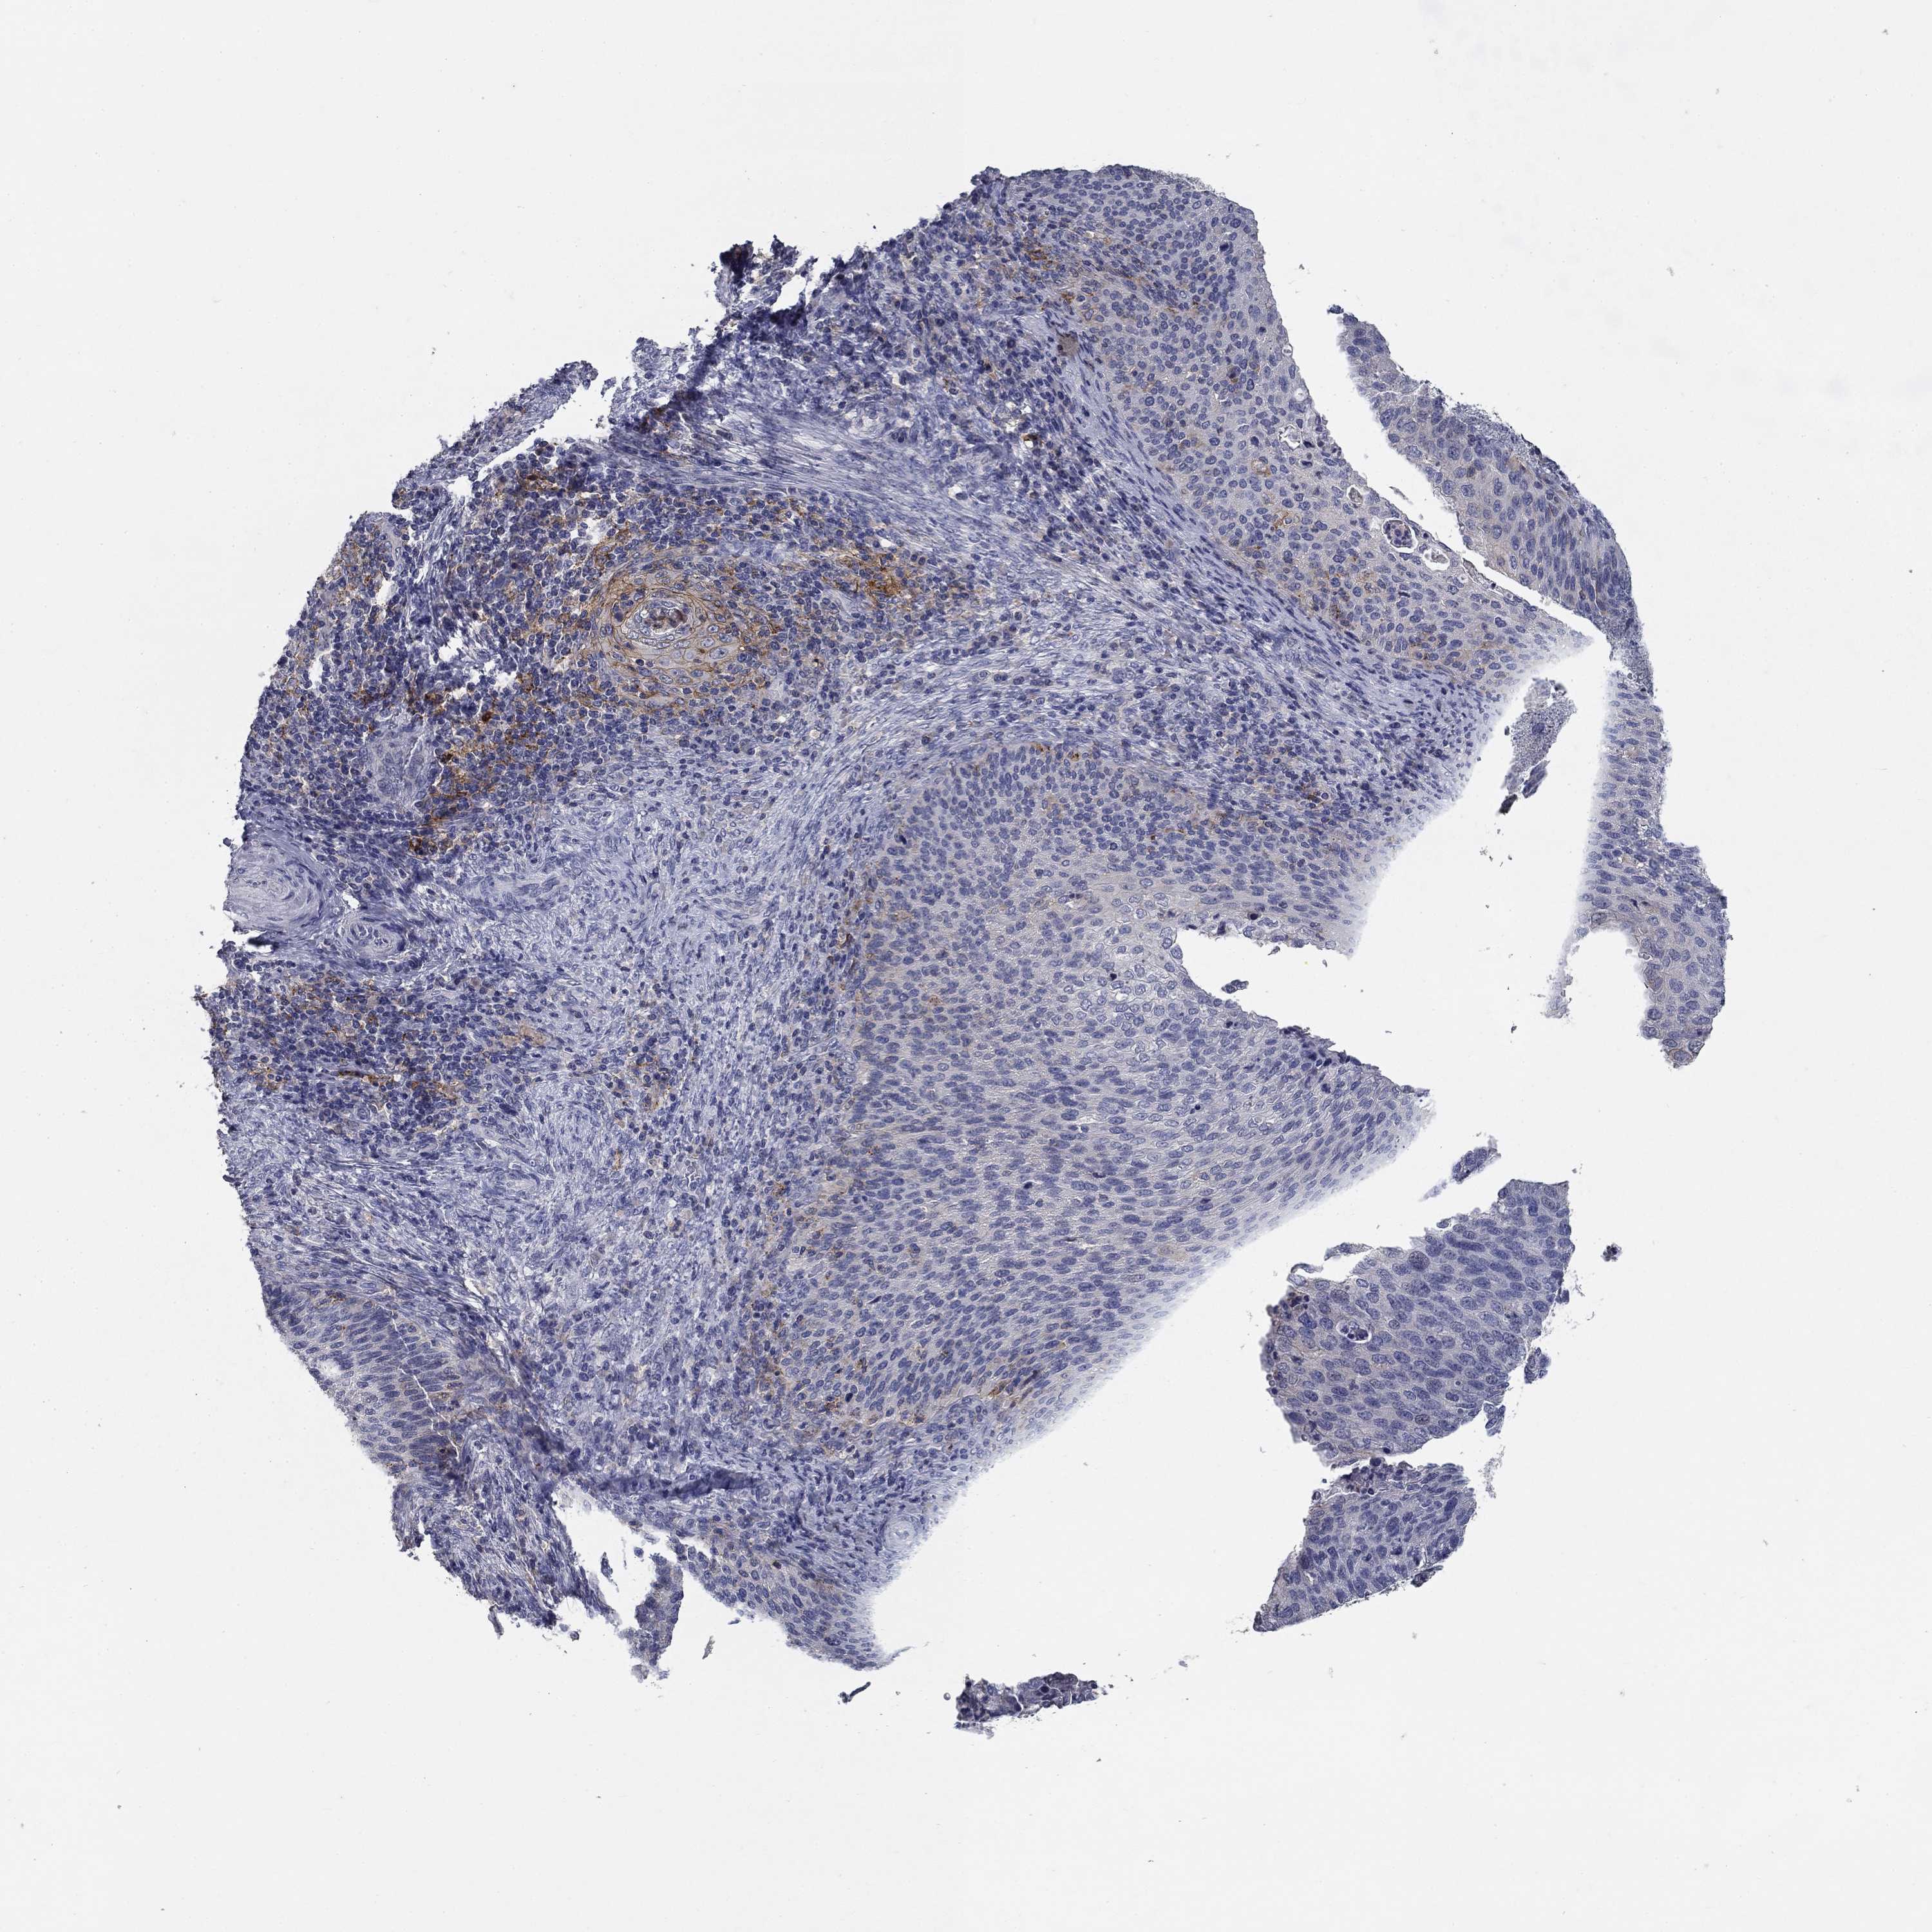

CERVICAL CANCER - Protein expressioni

A mouse-over function shows sample information and annotation data. Click on an image to view it in a full screen mode. Samples can be filtered based on level of antibody staining by selecting one or several of the following categories: high, medium, low and not detected. The assay and annotation is described here.

Note that samples used for immunohistochemistry by the Human Protein Atlas do not correspond to samples in the TCGA dataset.

Antibody stainingi

Antibody staining in the annotated cell types in the current human tissue is reported as not detected, low, medium, or high, based on conventional immunohistochemistry profiling in selected tissues. This score is based on the combination of the staining intensity and fraction of stained cells.

Each image is clickable and will lead to virtual microscopy that enables deeper exploration of all samples and also displays staining intensity scores, fraction scores and subcellular localization as well as patient and tissue information for each sample.

Antibody CAB076385

Antibody CAB080537

Staining

High

Medium

Low

Not detected

Intensity

Strong

Moderate

Weak

Negative

Quantity

>75%

75%-25%

<25%

None

Location

Nuclear

Cytoplasmic/membranous

Cytoplasmic/membranous,nuclear

Squamous cell carcinoma, NOS

Adenocarcinoma, NOS